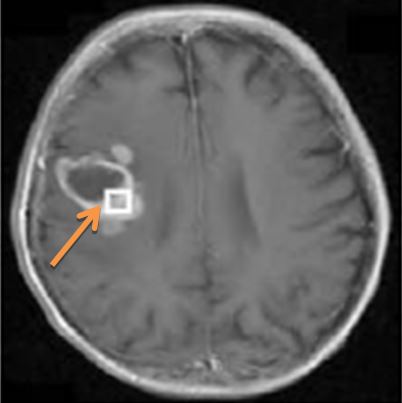

Bệnh nhân được tiến hành nội soi dạ dày tá tràng (hình 1)

Hình 1: Hình ảnh nội soi dạ dày tá tràng

Kết luận: Dịch dạ dày trong, niêm mạc dạ dày xung huyết, hang vị rải rác có trợt nông, mặt trước hành tá tràng có ổ loét đường kính 0,8cm bờ xung huyết, đáy có giả mạc; bấm sinh thiết có Helicobacter pylori - Hp (+)